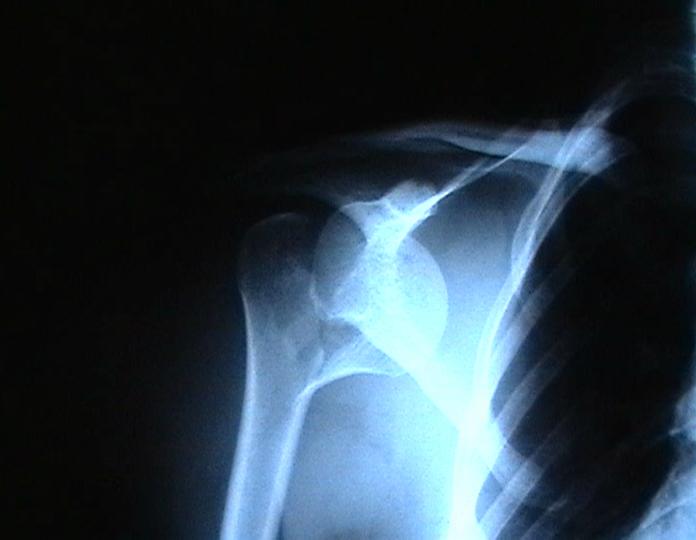

Мужчина 25 лет 16 августа 2002 г. в автоаварии получил перелом шейки плеча (снимок 1); 5 сентября в городской больнице выполнен остеосинтез пластинкой (снимок 2).К настоящему времени попал к нам на разработку ввиду выраженной контрактуры плечевого сустава. В течение последнего месяца беспокоят умеренные боли в области плечевого сустава, усиливающиеся при разработке, еще и торчит край пластинки. Нынешняя рентгенологическаякартина на снимках 3 и 4. Головка плеча уменьшается, сращение сомнительное.Кроме удаления пластинки, что еще на сегодня целесообразно сделать?Заранее спасибо.

Согласен с вашим мнением -асептический некроз головки плеча. Есть ли у вас надежды на реваскуляризацию головки ? Если надеетесь, то имеет смысл продолжать физио, если нет, то следует думать опротезировании.

I think the AVN is at least stage 3 with deformity of the head. I would advise a removal of implant and a cementless humeral head replacement. Or if you have the experience and the implant, as well as adequate bone stock, maybe a resurfacing prosthesis like the Copeland shoulder. I am not sure if you can do it one or two stages. You can perhaps do it in one stage if there is no sign of infection and if the patient condition allows it. You should not worry too much about age since this is a non

The current xrays indicate failure of the implant with losening. I would make sure there was no evidence of infection ( exam,ESR,CRP etc.) . I would agree with implant removal . I think this would be a suitable case for a circular ring fixator and compression, either a standard IIizarov or Taylor Spatial frame would be appropriate. I note from your previous cases that you have a high level of experience with this method.